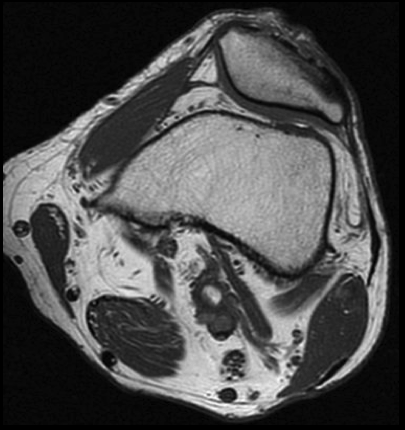

SE T1 AXIAL

3. Para confirmar los hallazgos de la angioTC de extremidades inferiores, se realizó RM de rodilla izquierda. ¿Qué hallazgo se observa en la secuencia axial SE T1?

- A. Aneurisma poplíteo trombosado.

- B. Quiste adventicial en la pared de la arteria poplítea.

- C. Banda muscular anómala rodeando a la arteria poplítea.

- D. Exóstosis de tibia comprimiendo la arteria poplítea.

- E. Flap intimal intraluminal.